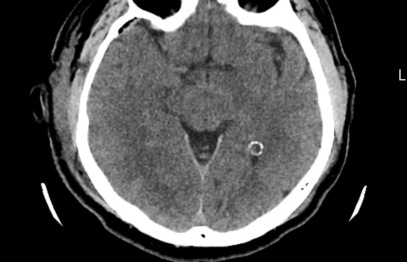

Pēc operācijas / Foto: publicitātes

Rezultāts: pēc operācijas pacientam pilnībā izzuda sūdzības, saglabājot redzi un acs kustīgumu.